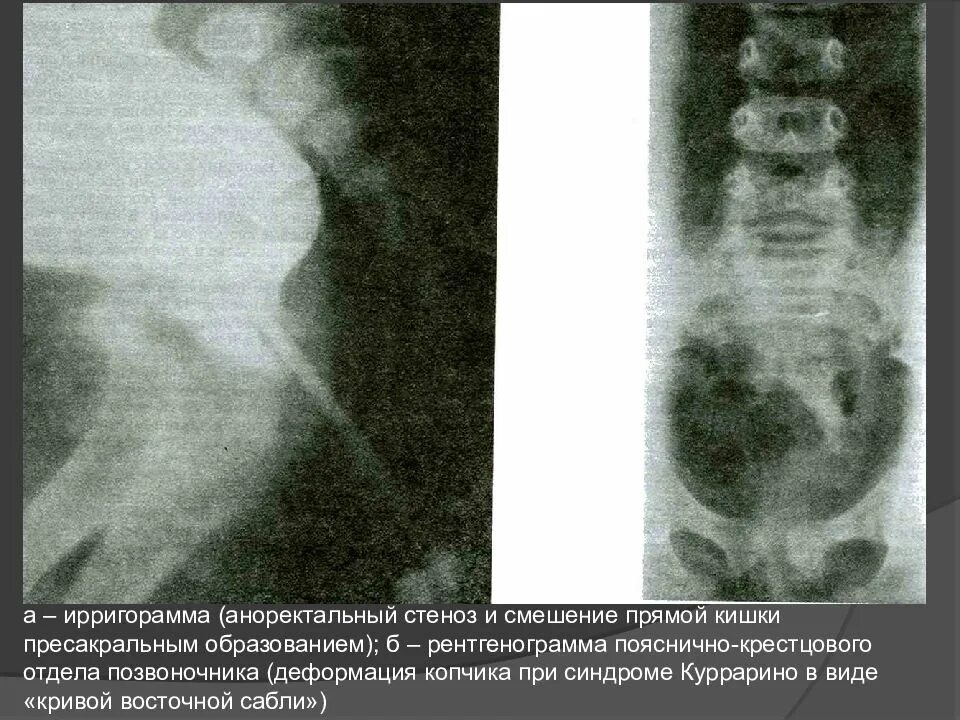

Спинномозговая грыжа